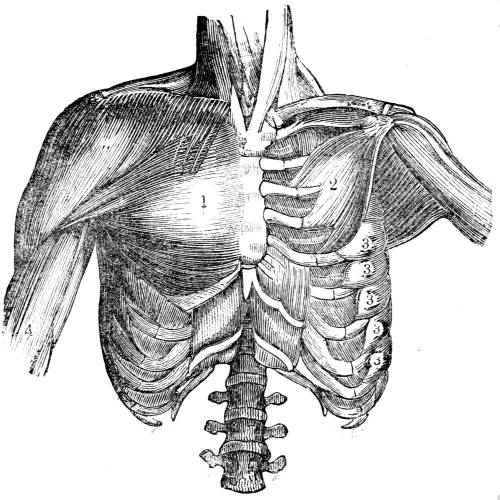

View of the intercostal muscles which fill up the interspaces

between the ribs. These muscles consist of a double

layer of fibres, the external and the internal, which cross

or intersect each other.

382. One part of the action of inspiration consists,

then, of this ascent of the ribs. The ascent

of the ribs is effected by the contraction of a

double layer of muscles called the intercostal (fig.

CXLII. ), placed in succession between each rib;

and which communicate this motion in the fol55lowing

mode. The first rib is fixed; the second

rib is moveable, but less moveable than the third,

the third than the fourth, and so on through the

series: consequently the contraction of the intercostal

muscles (figs. CXLII. and CXLVI. 2) must56

elevate the whole series, because the upper ribs

afford fixed points for the action of the muscles;

and so, when all these muscles contract together,

they necessarily pull the more moveable arches

upwards towards the more fixed (figs. CXLI. and

CXLVI. 2).